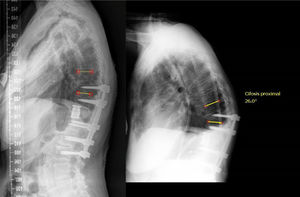

Dentro del grupo de la deformidad local (estadio 1), esta puede ser flexible (1A), si se observa una reducción de la angulación mayor del 50% en el decúbito con respecto a la radiografía (fig. 2) en bipedestación o rígida (1B), cuando no se ve una reducción con el decúbito (fig. 3)13. Por último, esta deformidad local, puede estar compensada (C) cuando la teleradiografía en bipedestación el SVA está en parámetros normales, o no compensada (NC), cuando la teleradiografía demuestra un SVA fuera de rango. Conviene recordar que el SVA está ajustado a la edad, y no buscamos una corrección tan exigente en el paciente anciano como en el paciente joven8.

En el grupo de la deformidad global (estadio 2), observamos pacientes cuya deformidad reduce en decúbito (fig. 4). Esto ocurre en parte por la flexibilidad (2A) de los discos intervertebrales o por la presencia de quistes de Kúmmell. Por otro lado, podemos estar ante deformidades globales rígidas (2B) en pacientes con espondilitis anquilopoyética o hiperóstosis difusa. A su vez, estos pacientes pueden estar compensados (C), o descompensados (NC).

Ilustración de un caso con un estadio 1BC, en el que se observa que compensa con un mecanismo de hiperlordosis lumbar (nótese una lordosis lumbar de 74° para una incidencia pélvica de 54°). Se trató con una osteotomía de decancelación y una instrumentación corta y se observa en la radiografía de control del 5° año posoperatorio una normalización de la hiperlordosis lumbar.